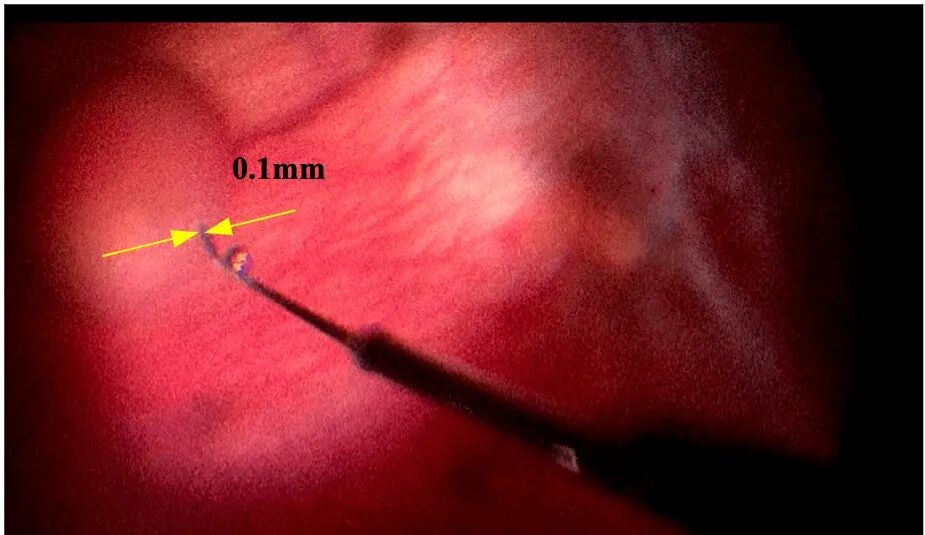

由浙江省人民医院眼科中心沈丽君教授,陈亦棋教授领导的眼底病手术团队,操作“迪视微锋”眼科手术机器人,通过外径100微米的显微注射针,在3分钟内将400微升溶栓药物重组组织纤溶酶原激活剂(rtPA)精准地注射到了患者眼底视网膜下腔中

术中OCT结果显示药物被精确递送至病灶部位,按照治疗计划成功地驻留在视网膜色素上皮层上方的下腔中,整个手术操作过程安全顺利,患者恢复良好。